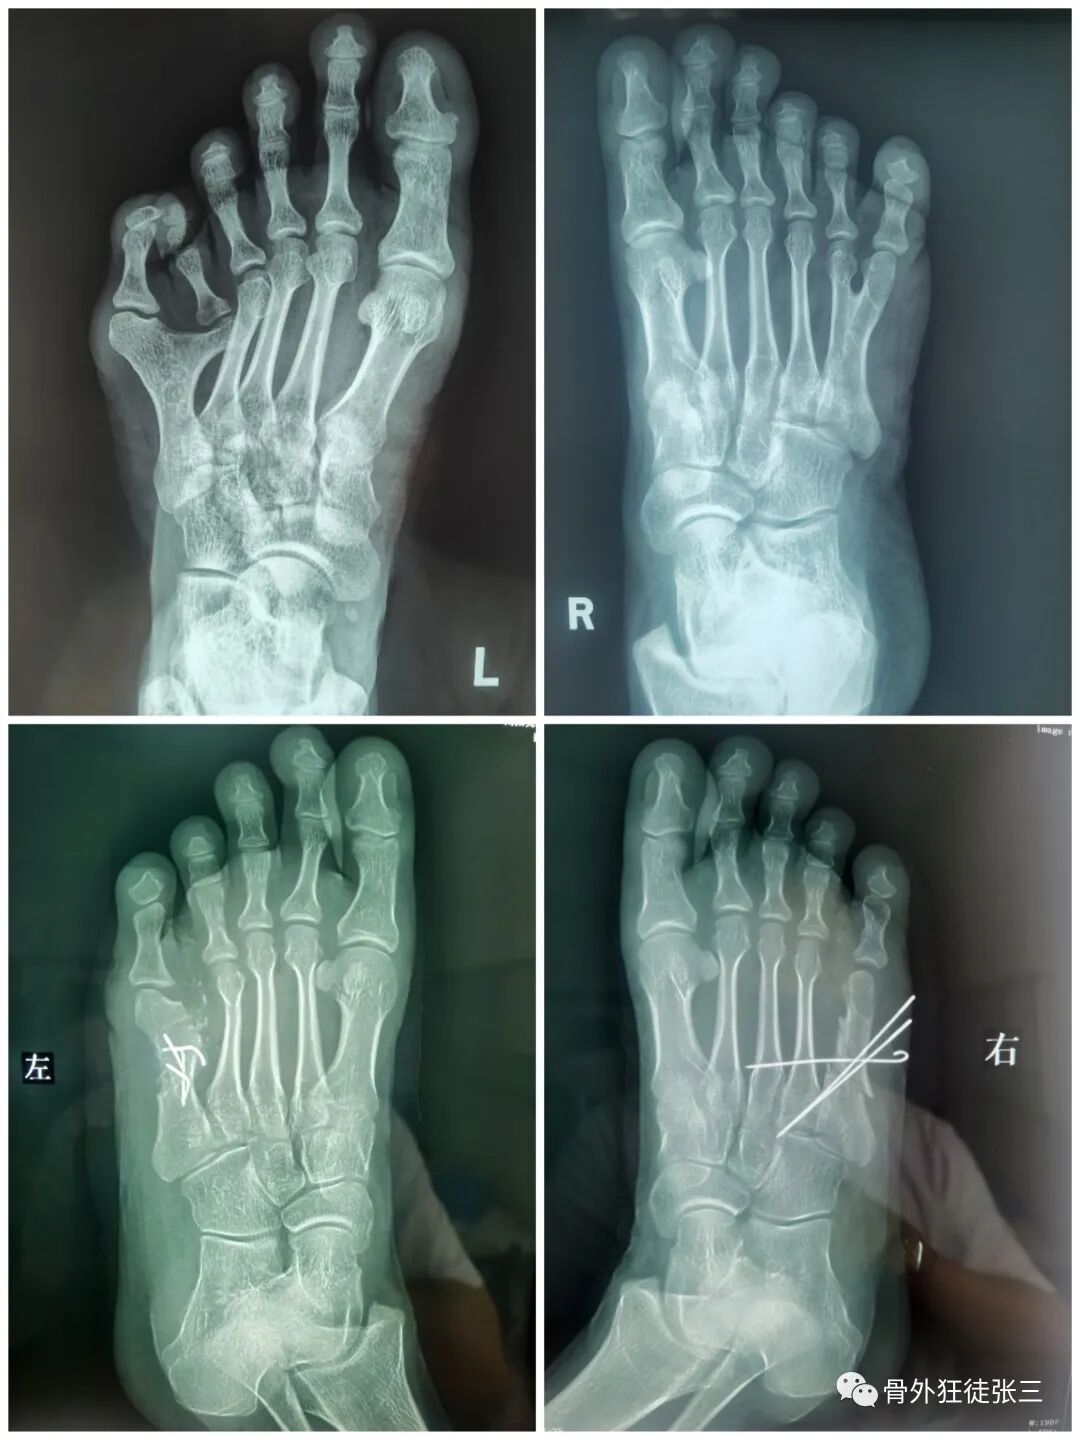

病例8,第234跖骨骨折,闭合穿针

病例33,开放性Lisfranc损伤+第2345跖骨骨折脱位